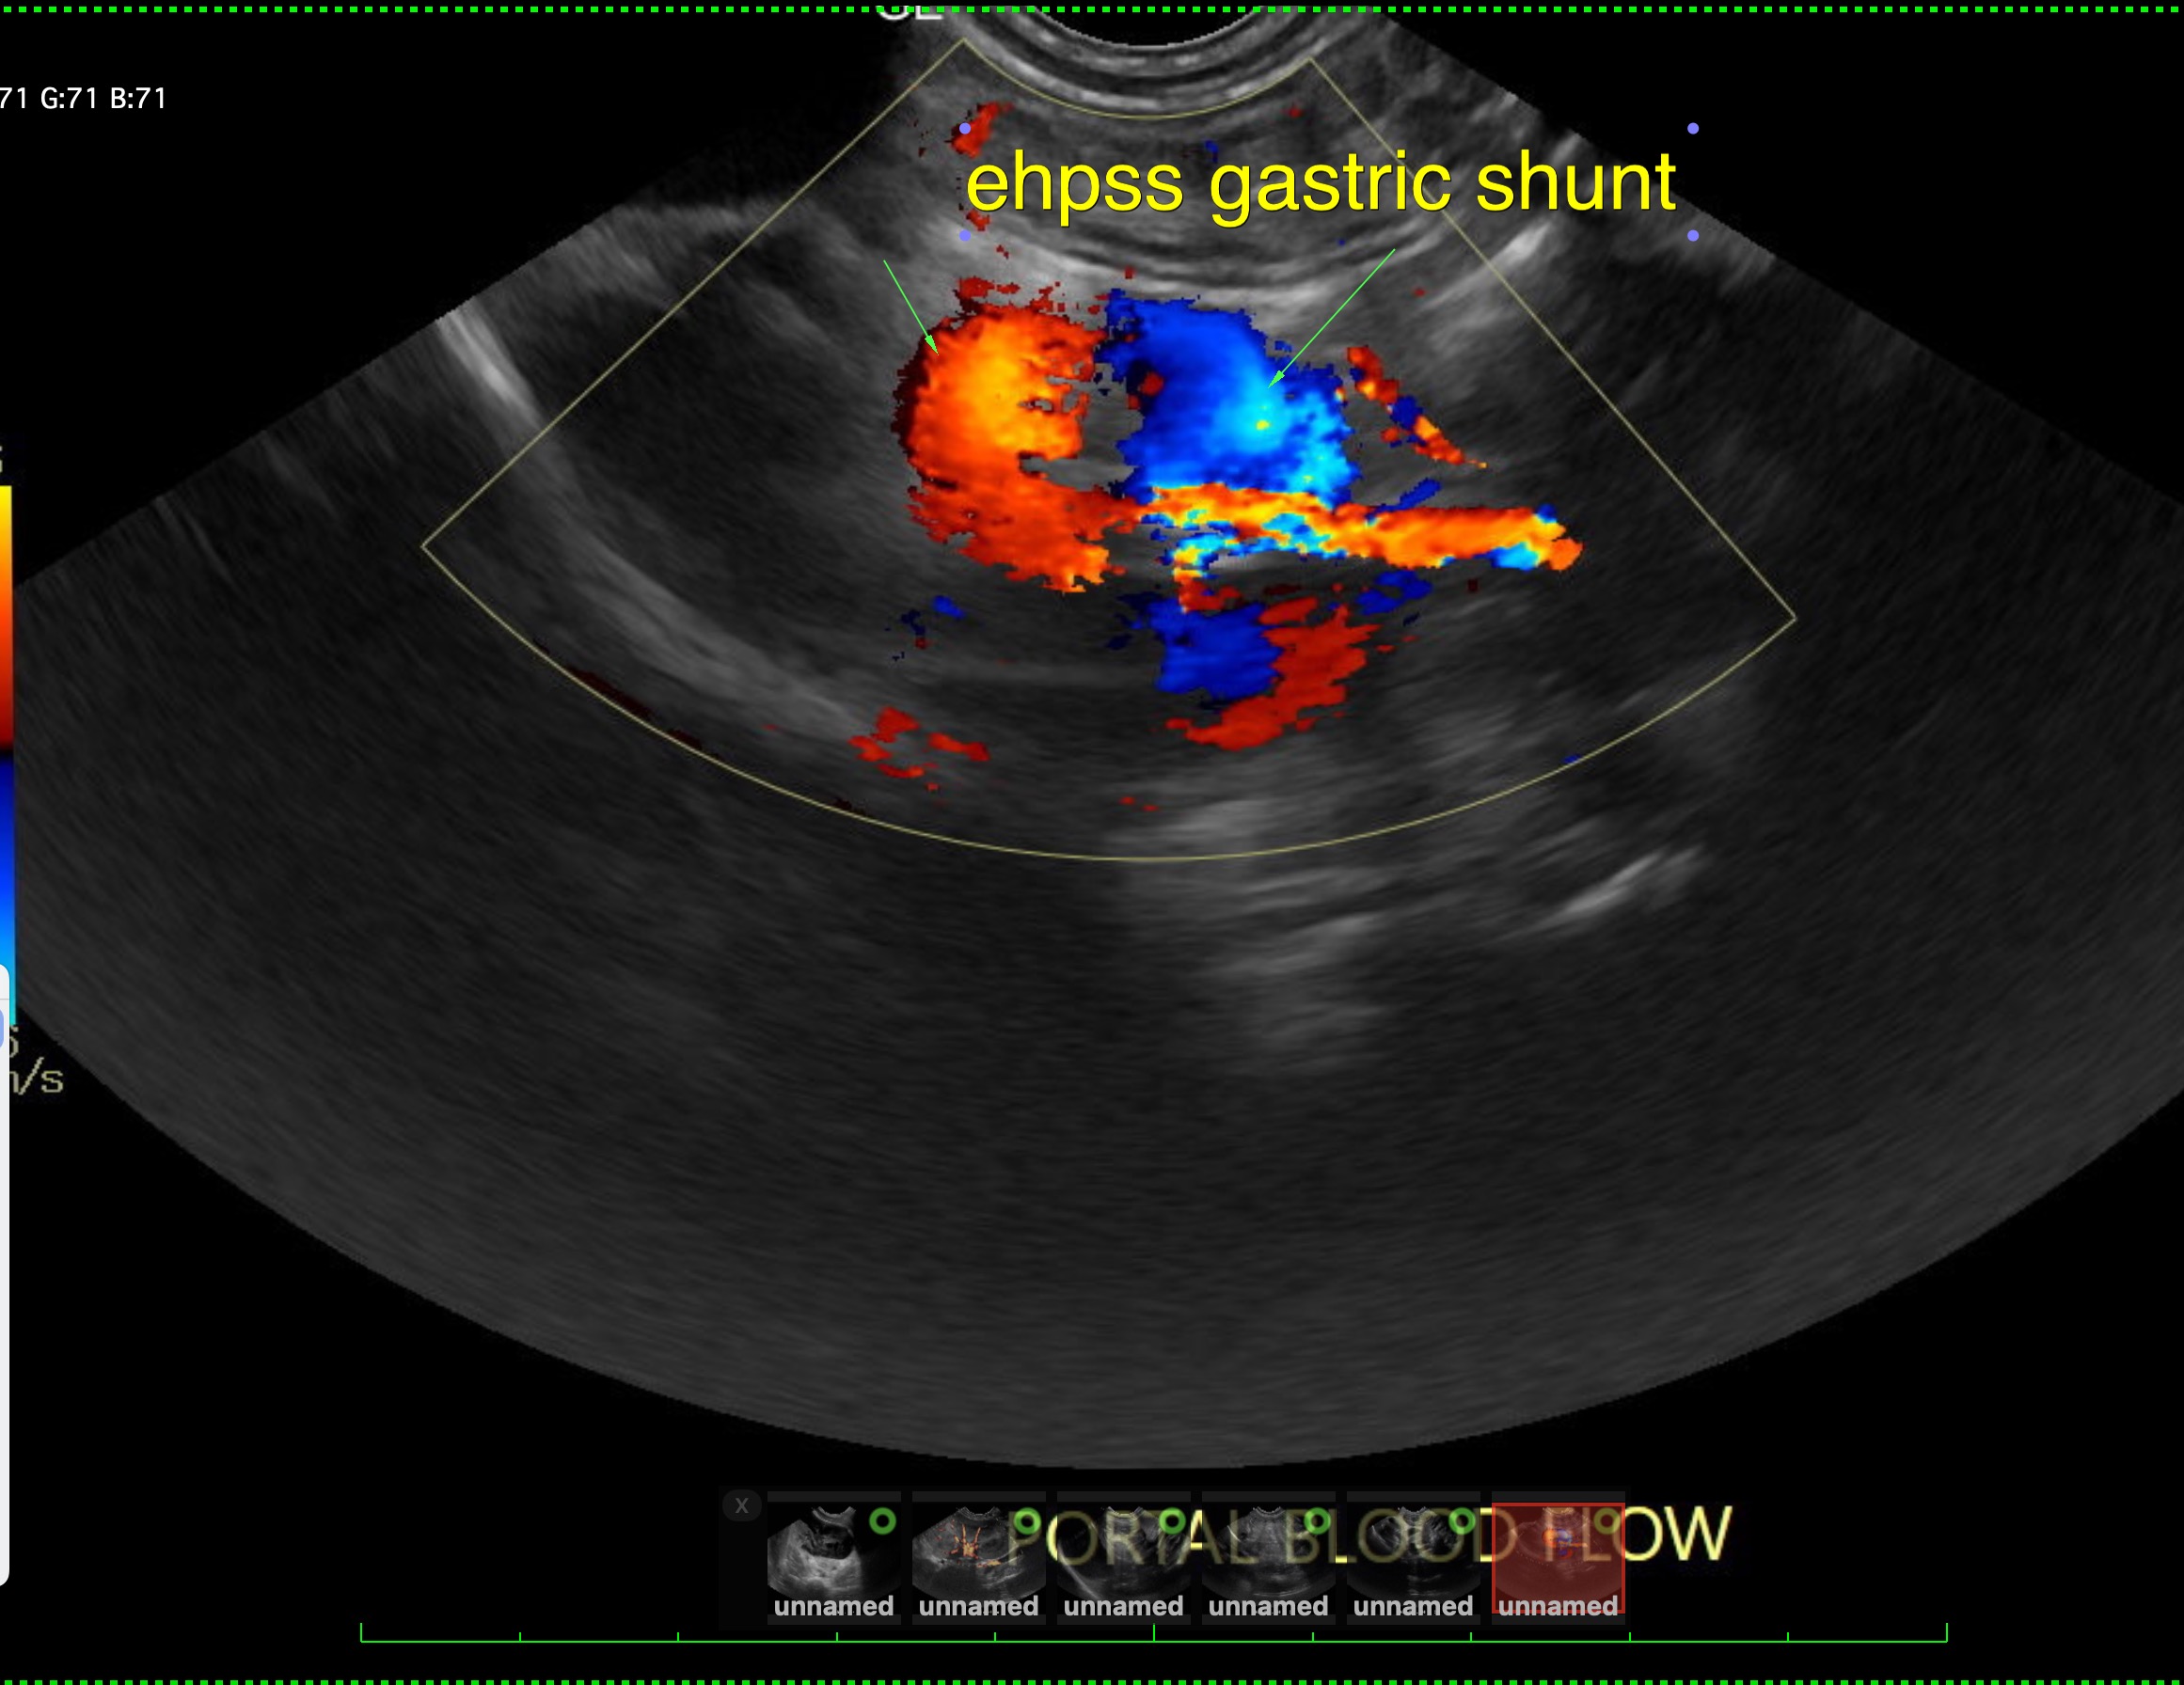

Labwork (fasted): TP 4.5, Alb 2.5, ALP 144, ALT 155, GGT 3, Bili 0.4, Cre 0.3, Cho 51, Amy 266 CBC – HCT 39%, Hgb 12.0 UA – USG 1.030pH 6, 1+ bilirubin, WBC 4-10/hpf, rods 26-50/hpf Negative Accuplex Bile Acids: Pre 299.2, Post-meal – 90.7